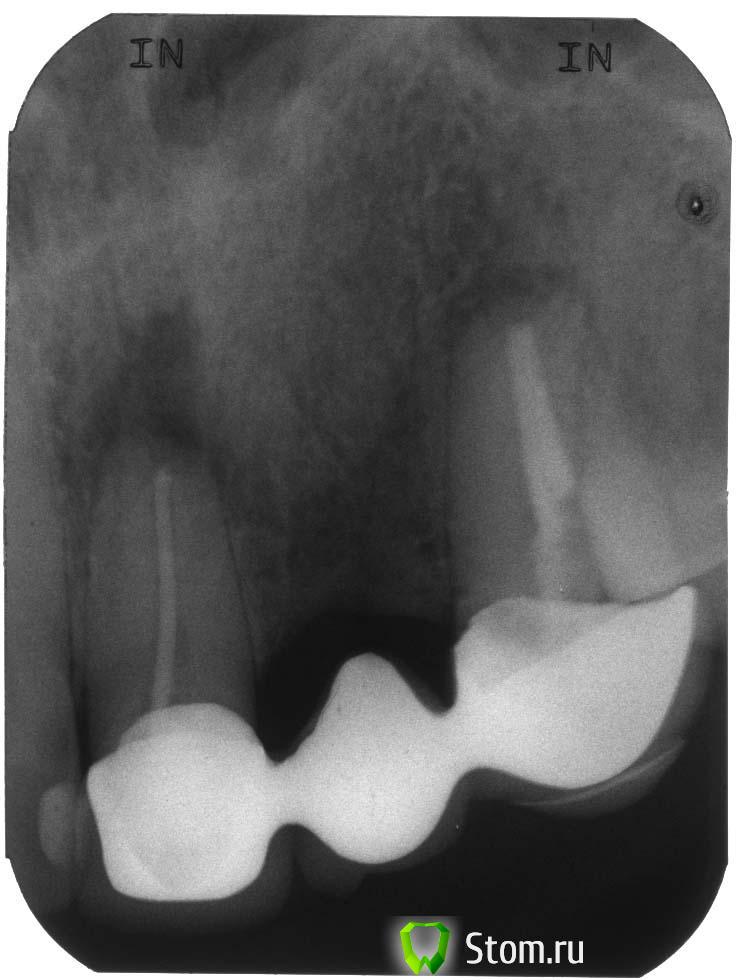

Здравствуйте. Я в первый раз собираюсь ставить импланты. У меня проблемы с передними верхними зубами. Начались они около 15 лет назад. Сначала выросла киста на левой верхней двойке. Сделали резекцию, но через несколько лет она снова выросла и перекинулась на соседние единицу и тройку. Пришлось удалить двойку и сделать резекцию единицы и тройки. Тогда же поставили мост, который стоит и сейчас(на фото). Но сейчас, со слов врача, опять выросла киста, уже в третий раз. Врач предлагает два варианта:

1)Я прикрепил файлы со снимками. Скажите, у меня действительно кисты и на единице и на тройке? И насколько там все плохо?

1. действительно, с зубами все не ах...